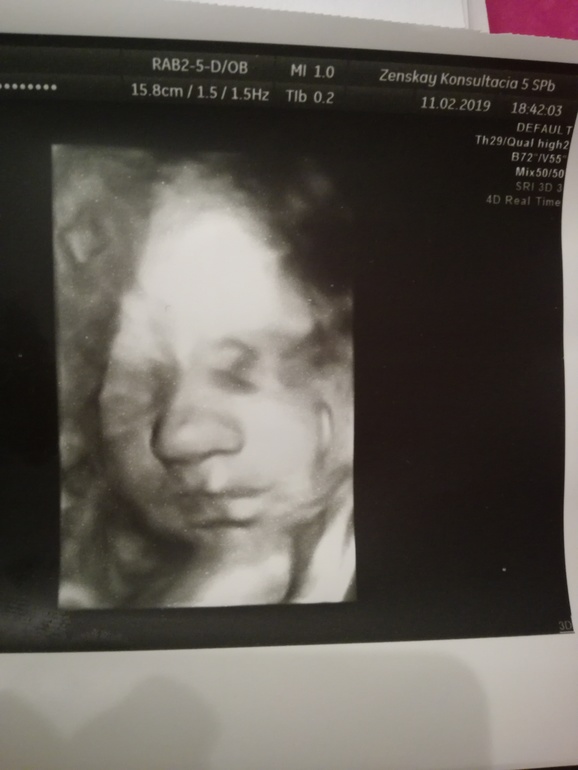

31-32 недели

УЗИ, КТГ, доплерЧувствую себя лучше. Вчера был 3 скрининг. Вес уже 1800 у нашего сынули. Предлежания не нашли. И наше фото😍. Он прекрасен.

Посмотрим какой родится). Для нас загадка карие или голубые глаза и волосы мои светлые и густые или папины темные и редкие).

Спасибо). Как то эта беременность у меня в тихую)). Почти не пишу ничего. Читаю, а писать не хочется. Удивительно самой😄. Я все налюбоваться малявкой не могу, такой красивый)).